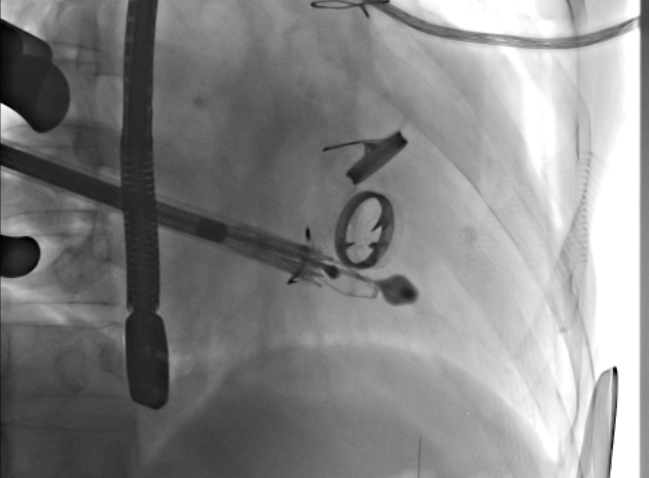

瓣膜植入前右心室造影

瓣膜植入后右心室造影

根据术前CT的测量结果,选择使用JS/TTVI-28-40型号的LuX-Valve®瓣膜。陆方林教授用导管顺利将介入瓣送入右心室,过三尖瓣瓣环到达右心室,精准地控制着输送系统,最终和超声确认无瓣周漏后对瓣膜进行锚定,术后超声和造影显示瓣膜位置良好,几乎无反流。

瓣膜植入术后右心室造影